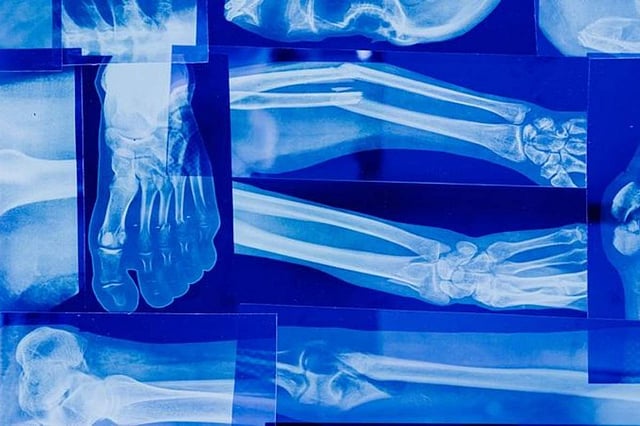

The fundamental underpinning of an active and healthy lifestyle lies in robust bones, which provide the structural framework for our bodies and safeguard vital organs. As the years advance, a natural decline in bone density unfolds, rendering bones more vulnerable to fractures and breaks.

In this article, we delve into the realm of bone fragility, a condition commonly known as osteoporosis, marked by diminished bone mass and compromised structural integrity. The intention is to unravel telltale indicators of weakening bones, enable you to proactively safeguard their bone health and forestall potential complications.

Among the conspicuous markers of weakened bones are recurrent fractures or breaks, frequently arising from minor accidents or tumbles. Those grappling with diminished bone strength often find fractures to be easily incurred and protracted in their healing. Detecting heightened susceptibility to fractures should prompt a medical evaluation to ascertain the underlying triggers.